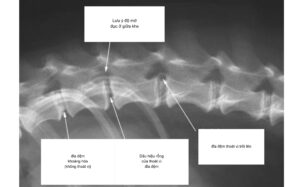

Bình thường x-quang ta khó phát hiện được đĩa đệm, hãy để ý khoảng

cách khe giữa các đốt sống